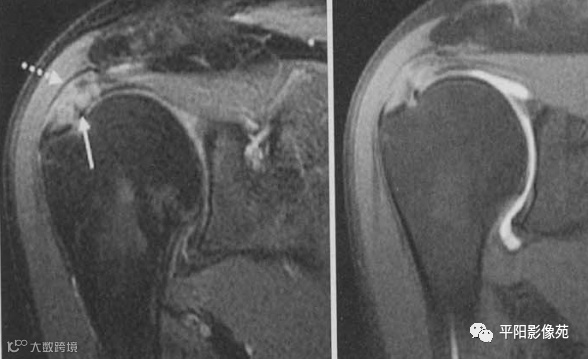

全层撕裂主要表现有:

肌腱连续性中断,裂隙由滑囊面贯穿至关节面,信号强度近似水信号强度,伴有肌腱回缩。

MR关节造影对一些容易漏诊或误诊为部分撕裂的小全层撕裂有较高的敏感性和特异性,当存在小全层撕裂时,MR关节造影能显示肌腱连续性中断,造影剂经过裂隙进入肩峰下-三角肌下滑囊内。

肌腱全层撕裂,示例

1、冈上肌肌腱全层撕裂,肌腱断端回缩

2、冈上肌肌腱全层撕裂,肌腱断端回缩,肩峰下-三角肌下滑囊积液